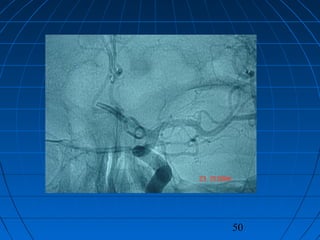

 56 yaşında erkek hasta56 yaşında erkek hasta

 BaşağrısıBaşağrısı (kronik-progresif, yaklaşık bir(kronik-progresif, yaklaşık bir

yıldır)yıldır)

 Nörolojik bakımdan normalNörolojik bakımdan normal

 Kranyal MRG:Kranyal MRG:

 pitüiter macroadenompitüiter macroadenom

 insidental AComA anevrizmasıinsidental AComA anevrizması

CERRAHİCERRAHİ

 Sol pterional trans-sylvian yaklaşımSol pterional trans-sylvian yaklaşım

 AcomA Anevrizması kliplendiAcomA Anevrizması kliplendi